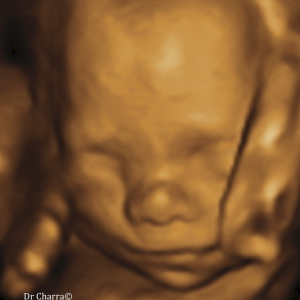

Suivi de votre grossesse avec réalisation des échographies recommandées, Prise en charge des IVG medicamenteuses (en lien avec la maternité de Beaune), infertilité, prise en charge des douleurs pelviennes (endométriose par exemple)

Diplômée en Echographie foetale et Gynécologique

Diplômée en Médecine Foetale

Agrément National pour la réalisation des échographies du Premier Trimestre de grossesse